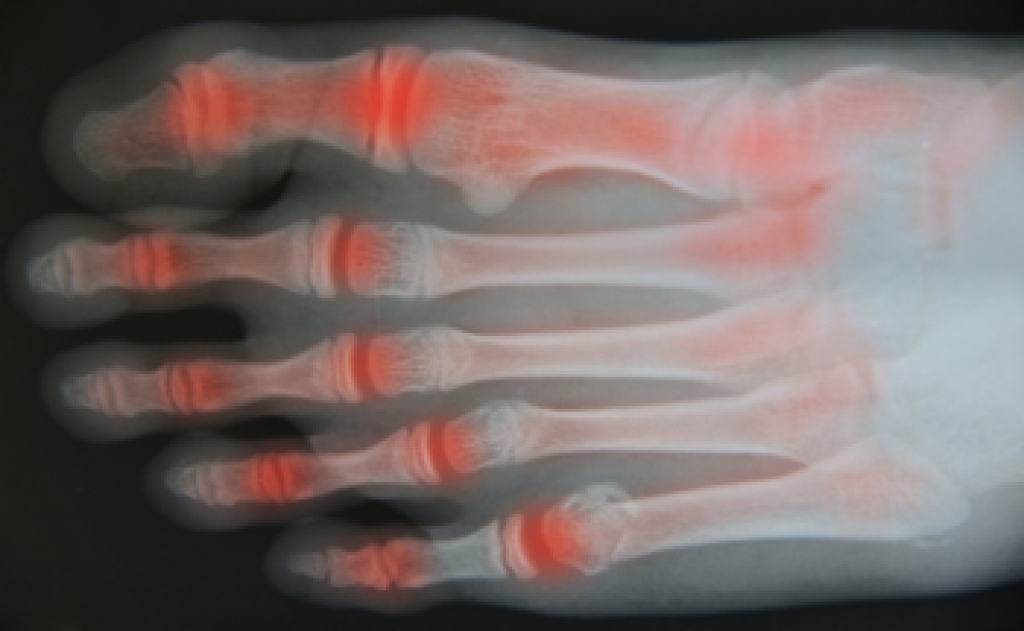

Shock wave therapy for plantar fasciitis is a non-invasive medical treatment designed to alleviate the excruciating heel pain caused by plantar fasciitis. Plantar fasciitis is a condition that is characterized by inflammation of the plantar fascia, a thick band of tissue connecting the heel bone to the toes. This inflammation results in stabbing pain, especially with the first steps in the morning. Shock wave therapy, also known as extracorporeal shock wave therapy, or ESWT, involves the application of high-energy shock waves to the affected area. These shock waves stimulate the body's natural healing processes by increasing blood flow and promoting tissue repair. Additionally, shock wave therapy may break down the calcium deposits that can form in the plantar fascia. This treatment is typically administered over several sessions, and its effectiveness varies from person to person. While it is considered safe, consulting a podiatrist is crucial in determining if shock wave therapy is the right choice for managing your plantar fasciitis. If you are interested in learning more about shockwave therapy, it is suggested that you confer with this type of doctor who can provide you with the information you are seeking.

Shockwave is recommended for patients suffering from heel pain and associated problems. Heel pain is a common condition which can be caused by obesity, overexertion, and spending a substantial amount of time on hard floors with your feet exposed and unsupported.